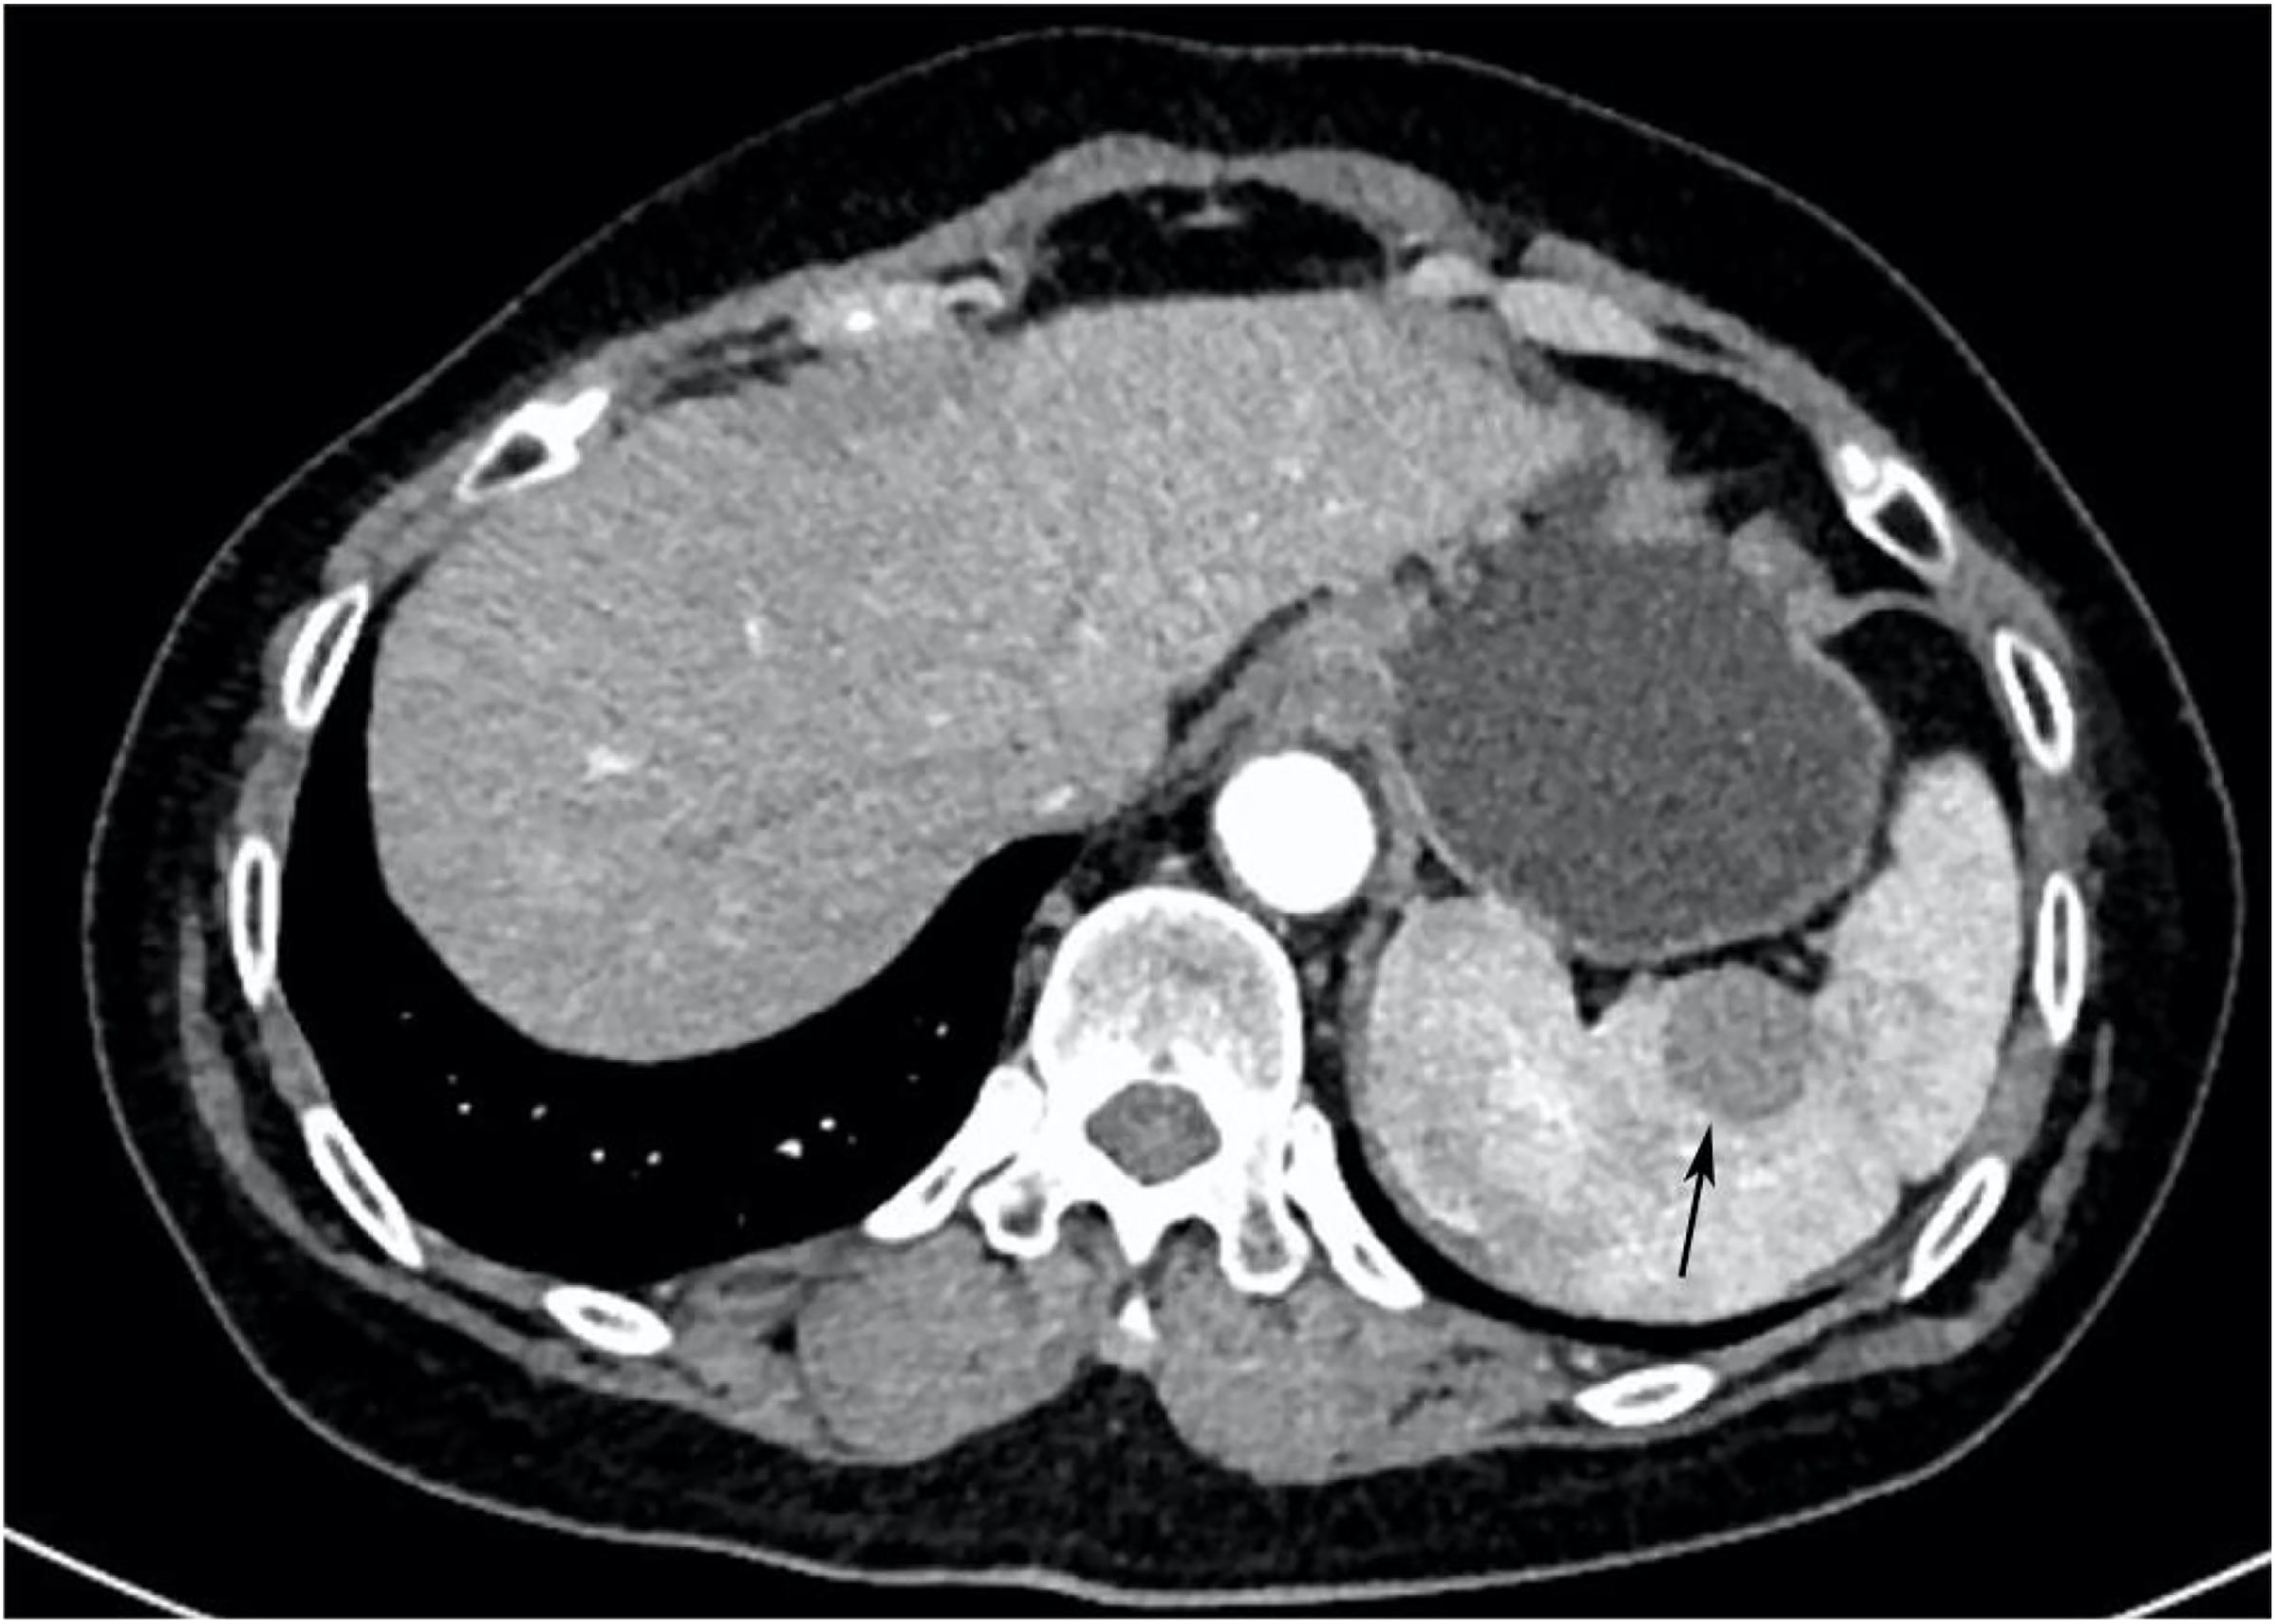

Ultrasonography conducted 2 years ago showed an enlarged spleen with 42 mm thickness and 145 mm length. The splenic parenchyma exhibited a diffusely thickened echotexture with a reticular pattern and no space-occupying lesions were identified. Two-dimensional ultrasonography conducted in our hospital showed an enlarged spleen, with approximately 52 mm thickness and 147 mm length, diffuse thickening and uneven distribution of the splenic parenchymal echo, and zonal or grid-shaped. A mass of size approximately 24 × 22 mm was detected at the hilum of the spleen. It showed irregular surface, with a very low internal echo, oval shape, and clear boundary. Color Doppler flow imaging revealed a weak blood flow signal in the mass located at the splenic hilum, with no apparent abnormality in the blood flow signal in the spleen (Figure 1). To further qualitatively diagnose the mass located at the splenic hilum, CEUS was performed after receiving patient consent. Following the infusion of the contrast agent SonoVue, the mass located at the splenic hilum began to show inhomogeneous enhancement (low enhancement) in the arterial stage, with a clear enhanced edge. The enhancement reached the peak at 17 s, and the peripheral splenic tissue showed enhanced uniformity as compared to the mass. At the venous stage, the mass began to show a decline in enhancement at 24 s. Compared to the peripheral splenic tissue, regression of the tumor mass was delayed, and the overall enhancement pattern was slow-in and fast-out, as shown in Figure 2. Combined with the results of CEUS, the final diagnosis was splenomegaly with splenic lymphoma. Needle biopsy was recommended if necessary. CT imaging revealed an enlarged spleen with uneven distribution; two isodense enhanced foci were observed in the spleen, with the larger one showing a diameter of approximately 20 mm (Figure 3). Bone marrow aspiration showed the following pathological findings: CD20(+; a small number of B lymphocytes), CD3(−), CD138(−), and CD38(−). Bone marrow hyperplasia was slightly reduced.

Figure 3. CT image. The spleen was enlarged and unevenly distributed; two isodense enhanced foci were observed in the spleen, with the larger one having approximately 20 mm diameter (indicated by the arrow).